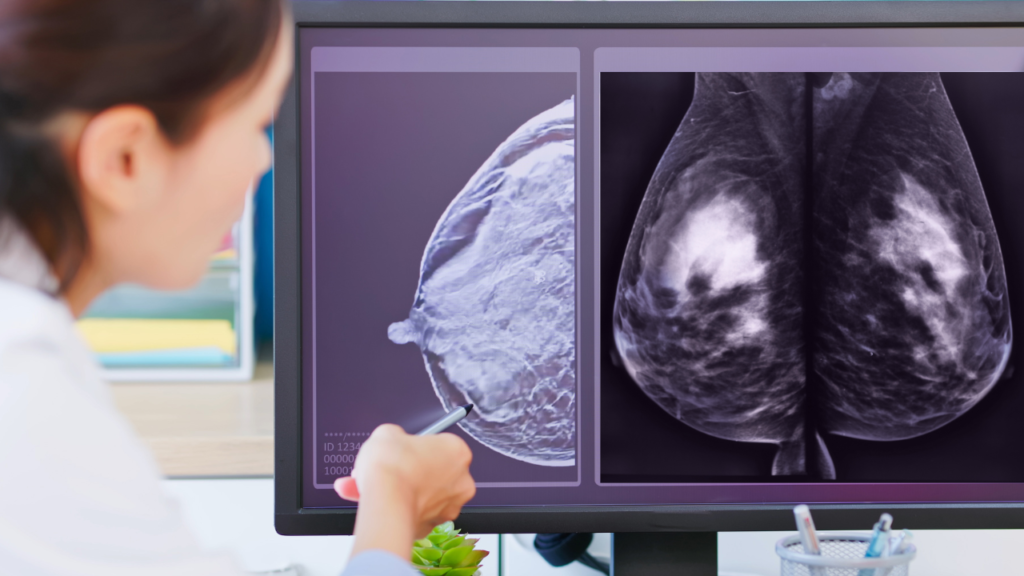

Subspecialty Reads Across Mammography, Ultrasound, MRI and CEM

Breast imaging relies on precise interpretation of modality-specific findings such as microcalcifications, mass morphology, enhancement patterns, and interval change. RadWorks provides subspecialty reads that support screening programs, callback evaluations, and staging or follow-up in suspected or confirmed breast disease.

• Screening mammography (2D & 3D tomosynthesis): Early detection of calcifications, asymmetries, and architectural distortion.

• Diagnostic mammography: Targeted evaluation for symptoms or abnormal screens.

• Breast ultrasound: Characterization of solid and cystic lesions, axillary assessment.